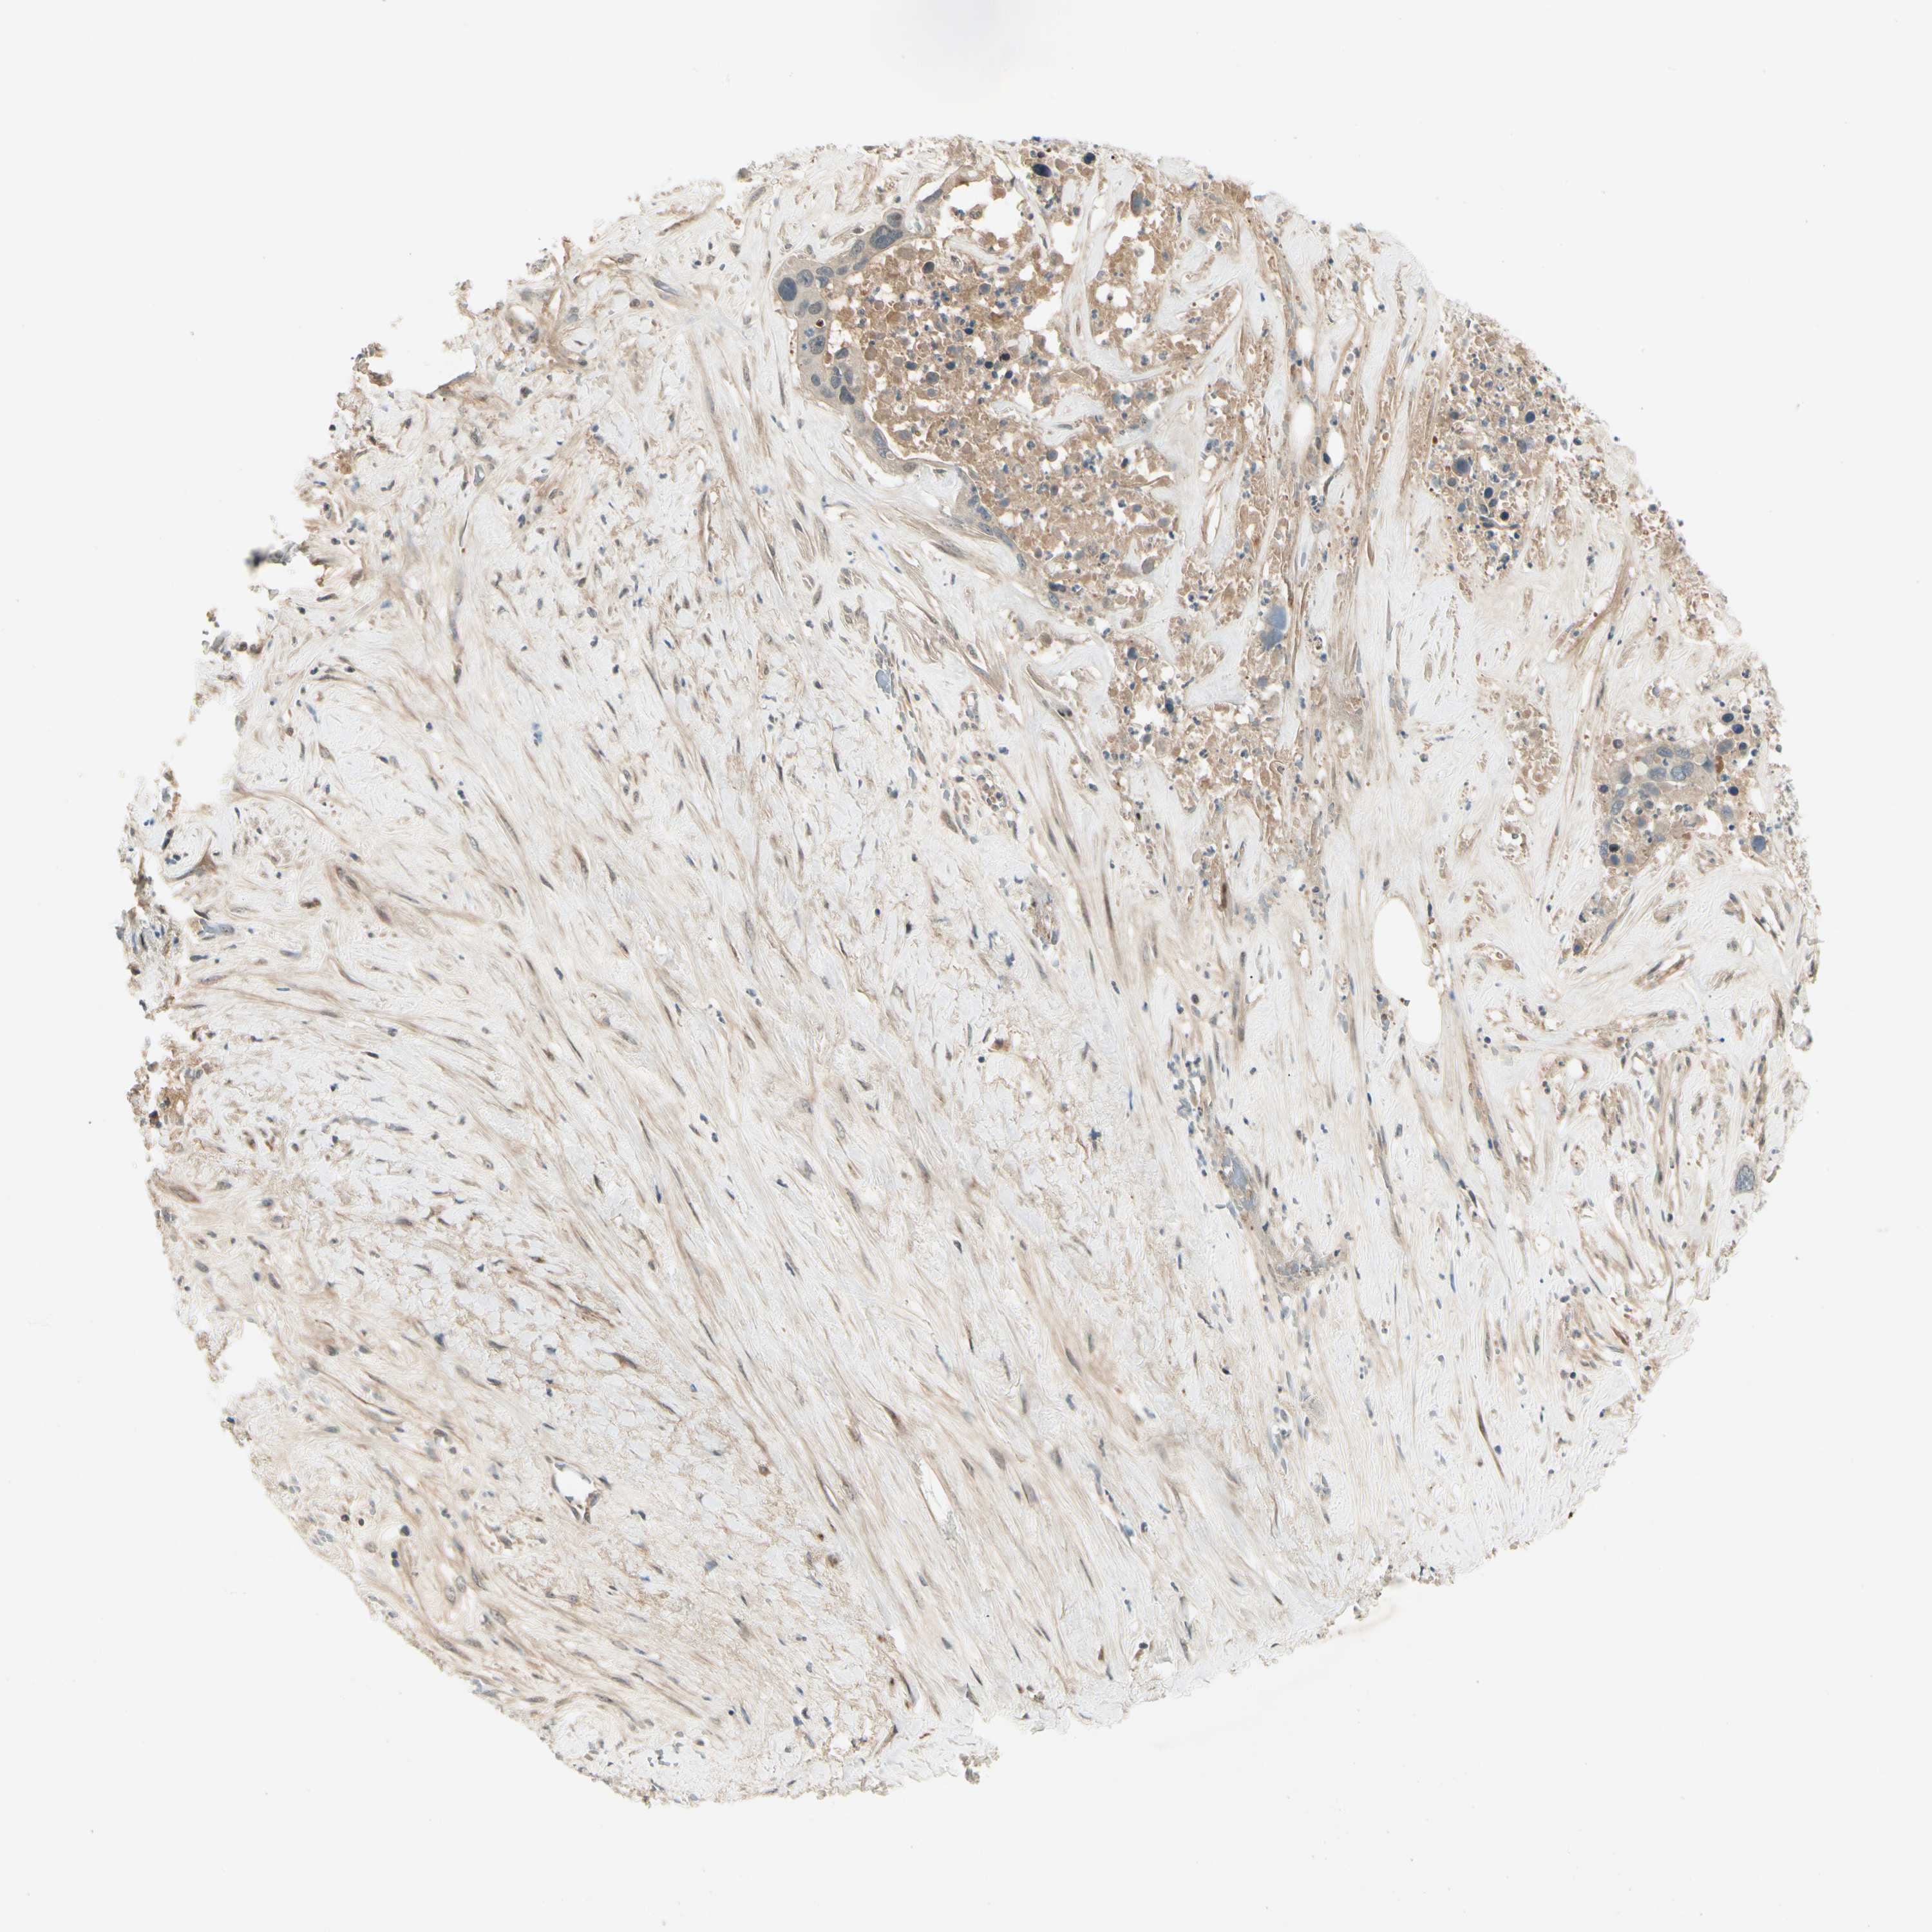

LIVER CANCER - Protein expressioni

A mouse-over function shows sample information and annotation data. Click on an image to view it in a full screen mode. Samples can be filtered based on level of antibody staining by selecting one or several of the following categories: high, medium, low and not detected. The assay and annotation is described here.

Note that samples used for immunohistochemistry by the Human Protein Atlas do not correspond to samples in the TCGA dataset.

Antibody stainingi

Antibody staining in the annotated cell types in the current human tissue is reported as not detected, low, medium, or high, based on conventional immunohistochemistry profiling in selected tissues. This score is based on the combination of the staining intensity and fraction of stained cells.

Each image is clickable and will lead to virtual microscopy that enables deeper exploration of all samples and also displays staining intensity scores, fraction scores and subcellular localization as well as patient and tissue information for each sample.

Antibody HPA007698

Antibody HPA008184

Antibody CAB034350

Staining

High

Medium

Low

Not detected

Cholangiocarcinoma

Carcinoma, Hepatocellular, NOS